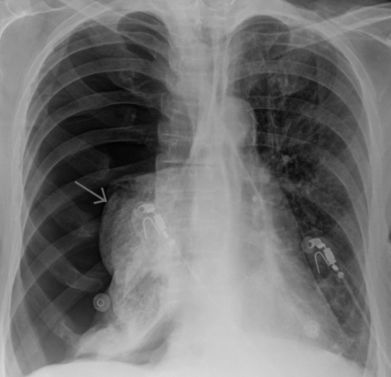

Пневмоторакс

Характер и локализация боли

Для пневмоторакса характерна острая боль в грудной клетке, которая усиливается при вдохе.

Иногда болевой синдром иррадиирует в плечо и спину со стороны пораженного органа.

Дополнительные симптомы

О начале заболевания говорит внезапно возникшая одышка. Далее пациент отмечает:

- сухой кашель;

- тахикардию;

- появление холодного липкого пота по телу;

- паническую атаку;

- резкую общую слабость.

При значительном нарушении кровообращения и дыхания отмечается синюшность кожи.

При открытом пневмотораксе (попадание воздуха через открытую рану грудной клетки) при вдохе слышится свистящий звук из раны.

При выдохе воздух выходит через открытую рану.

Диагностика и лечение

Диагностика патологии состоит из:

- осмотра пациента;

- рентгенографии грудной клетки;

- компьютерной томографии;

- исследования газового состава крови;

- ЭКГ.

Наличие незначительного объема воздуха в плевральной полости, при котором механизм дыхания не нарушен, как правило, не требует лечения.

В других случаях лечение проводится следующими способами:

- плевральная пункция, при которой отсасывается воздух;

- установка дренажной трубки;

- использование обезболивающих препаратов;

- кислородотерапия;

- оперативное лечение.